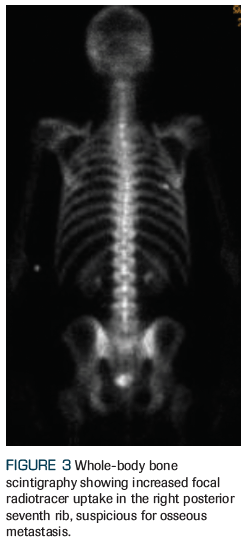

Figure 3. Whole-Body Bone Scintigraphy Showing Increased Focal Radiotracer Uptake

An otherwise healthy 59-year-old man who was recently diagnosed with American Joint Committee on Cancer (AJCC) 8th edition clinical stage IVB (T3aN1M1b) prostate adenocarcinoma presents to the radiation oncology clinic for consideration of radiation therapy. After he was found to have an elevated prostate-specific antigen (PSA) level of 16.7 ng/mL, he underwent a standard transrectal ultrasound–guided biopsy that revealed a prognostic grade group 4 (Gleason score 4+4) in 7 of 12 core biopsies, with lower-grade adenocarcinoma present in the remaining 5 core biopsies. A multiparametric prostate MRI revealed a large (4 cm) Prostate Imaging Reporting and Data System (PIRADS) 5 lesion with extracapsular extension, as well as pelvic lymphadenopathy, including a 2.2-cm left internal iliac node (Figures 1 and 2). A staging bone scan showed focal uptake in the seventh right rib (Figure 3), corresponding to a sclerotic lesion on follow-up CT, which was deemed highly suspicious for an isolated focus of metastatic prostate cancer after careful review in multidisciplinary conference. He was started on upfront systemic therapy with leuprolide, abiraterone acetate, and prednisone. Three months later, his PSA level had decreased to 0.03 ng/mL, and 1 month after that, imaging showed a mixed response to systemic therapy with reduced bilateral pelvic lymphadenopathy and persistent focal uptake in the seventh right rib metastatic lesion. No new lesions were identified.

After a discussion of the pros and cons of various management options, the patient elected to proceed with fractionated radiotherapy to the pelvis and SBRT to the bone lesion (Figures 4 and 5), along with continuous GnRH agonist therapy with abiraterone acetate plus prednisone. The patient tolerated radiotherapy well, with no significant toxicity. At this time, he is still receiving adjuvant ADT, with a PSA level < 0.01 ng/mL. We plan to discontinue ADT and allow testosterone recovery after completion of 24 months of continuous therapy.